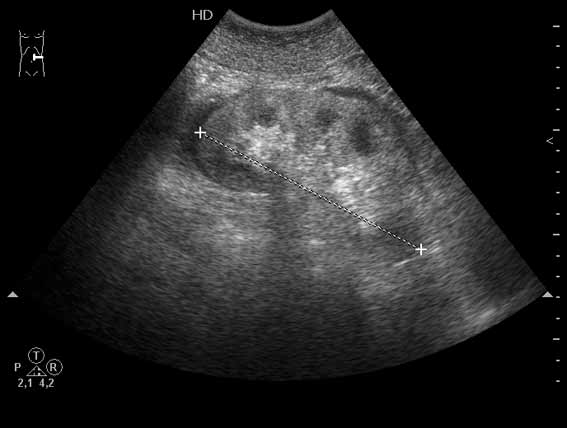

Женщина средних лет. В состоянии алкогольного опьянения уснула на корточках. Через несколько часов почувствовала онемение мышц и сильные мышечные боли.

Мышцы плотные на ощупь. При УЗИ сосудов имеются признаки компрессии вен увеличенными мышцами, острый тромбоз вен левой голени.

В общем анализе мочи - белок 2 г\л, микрогематурия, миоглобинурия.

Суточный диурез 500 мл.

Выявлены симметричные изменения обеих почек (см сонограмму и видеоклип).

М,б. коллега Uzgraph сможет объяснить, почему в "нормальной" почке заметно повышена эхоплотность коркового слоя паренхимы, и усилена кортико-медуллярная дифференцировка. Какие механизмы в рамках нормальной физиологии почки обеспечивают этот феномен.

Что видим:

1. Почки симметрично увеличены

2. Паренхима утолщена, эхогенность коркового вещества повышена

3. Пирамиды увеличены в размерах

4. Анамнез-клиника- ОАМ :arrow: т.н ренальный тип ОПН?

Наблюдается синдром позиционной компрессии, или позиционного сдавления, возникающий в результате длительного неподвижного положения тела пострадавшего, находящегося в бессознательном состоянии (кома, отравление и т.п.) или в состоянии глубокого патологического сна. При этом ишемия развивается от сдавления релаксированных тканей массой собственного тела....В ранних стадиях С. д. с. в первую очередь поражаются почки, что проявляется деструкцией эпителия канальцев, стазом и тромбозом как в корковом, так и мозговом веществе. Значительные дистрофические изменения развиваются в почечных канальцах, просветы которых заполняются продуктами распада клеток. Миоглобин и образующийся при гемолизе эритроцитов свободный гемоглобин усиливают ишемию коркового вещества почек, что способствует прогрессированию процесса и развитию острой почечной недостаточности....это к патогенезу возникновения изменений УЗ-картины почек +результаты ОАМ >>>картина ОПН